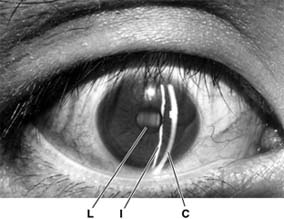

Figure 2-5

Figure 2-5: Slitlamp photograph of a normal right eye. The curved slit of light to the right is reflected off of the cornea (C), while the slit to the left is reflected off of the iris (I). As the latter slit passes through the pupil, the anterior lens (L) is faintly illuminated in cross section. (Photo by M Narahara.)

The patient is seated while being examined, and the head is stabilized by an adjustable chin rest and forehead strap. Using the slitlamp alone, the anterior half of the globe-the "anterior segment"-can be visualized. Details of the lid margins and lashes, the palpebral and bulbar conjunctival surfaces, the tear film and cornea, the iris, and the aqueous can be studied. Through a dilated pupil, the crystalline lens and the anterior vitreous can be examined as well.

Because the slit beam of light provides an optical cross section of the eye, the precise anteroposterior location of abnormalities can be determined within each of the clear ocular structures (eg, cornea, lens, vitreous body). The highest magnification setting is sufficient to show the abnormal presence of cells within the aqueous, such as red or white blood cells or pigment granules. Aqueous turbidity, called "flare," resulting from increased protein concentration can be detected in the presence of intraocular inflammation. Normal aqueous is optically clear, without cells or flare.